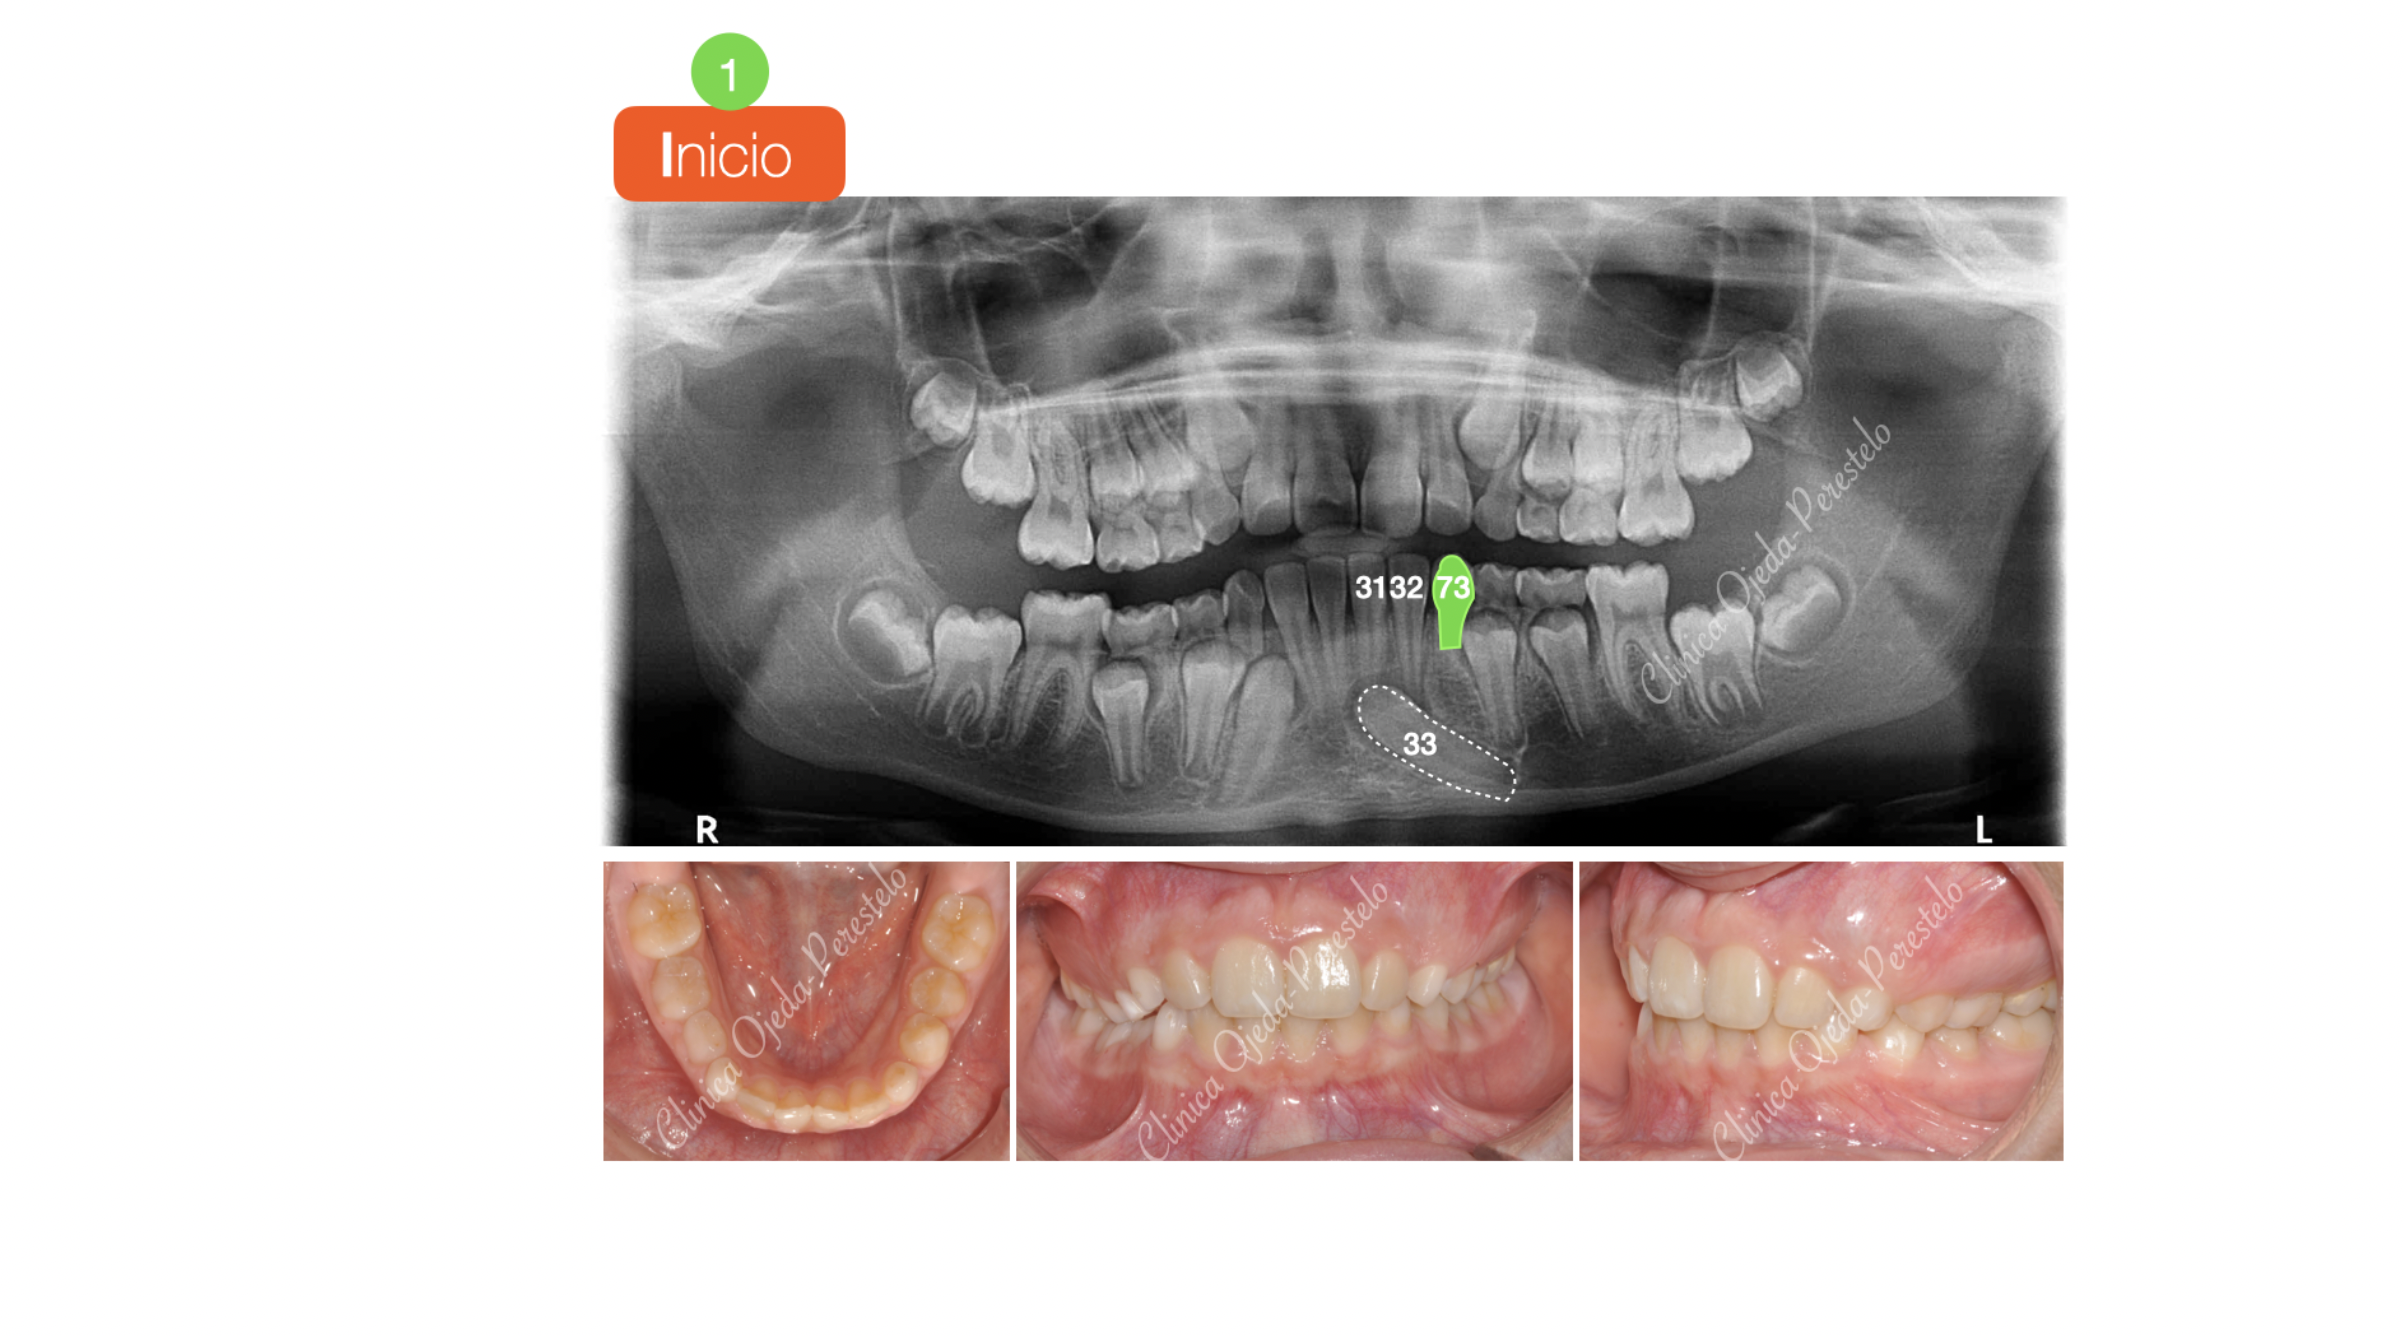

Canino Mandibular Retenido (33)

Presentamos a una adolescente con el canino mandibular izquierdo retenido y sin posibilidad alguna de erupcionar de manera natural.